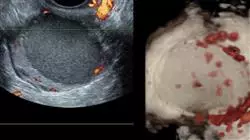

- 从临床实践的角度,深入探讨子宫内膜异位症的不同诊断方法。分析综合诊断标准

- 进一步诊断月经过多。了解所使用的辅助测试。了解鉴别诊断